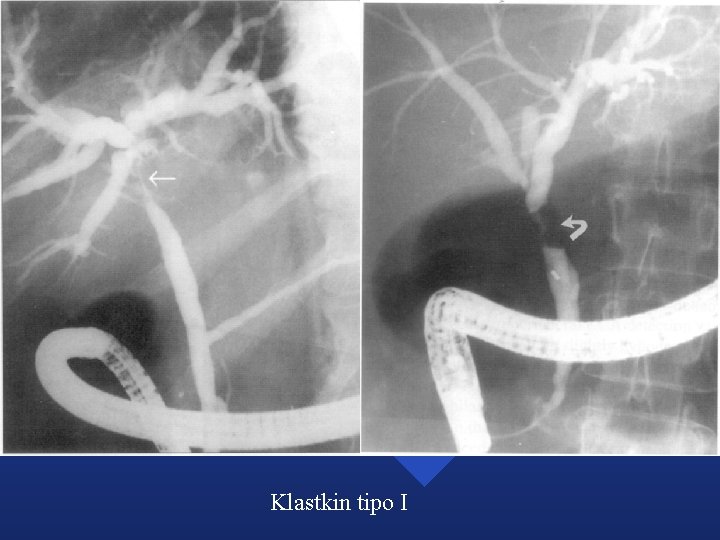

Tumores Biliares n Colangiocarcinoma – Intrahepático – Hiliar o tumor de Klatskin » Tipo I - Hepático común » Tipo II - Bifurcación » Tipo III a - Bifurcación y secundarios derechos » Tipo III b - Bifurcación y secundarios izquierdos » Tipo IV - Bilateral y conductos biliares secundarios – Extrahepático n Carcinoma vesicular

Klastkin tipo I